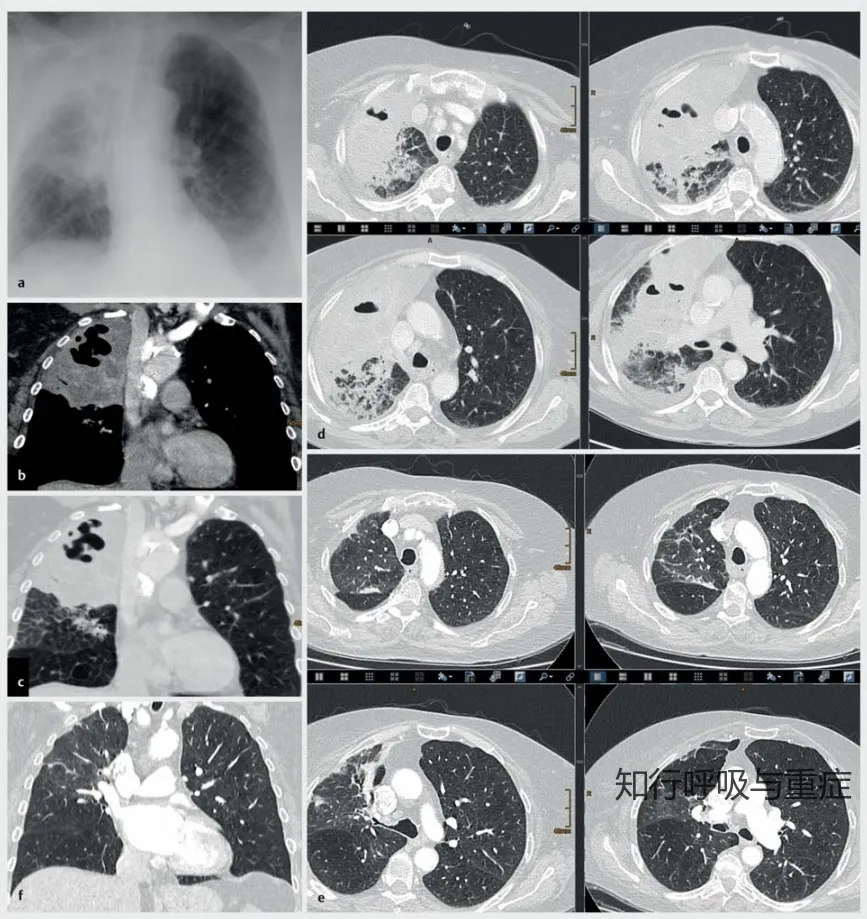

2)评估:胸部X线和CT扫描有助于诊断肺脓肿。

肺脓肿的CT扫描